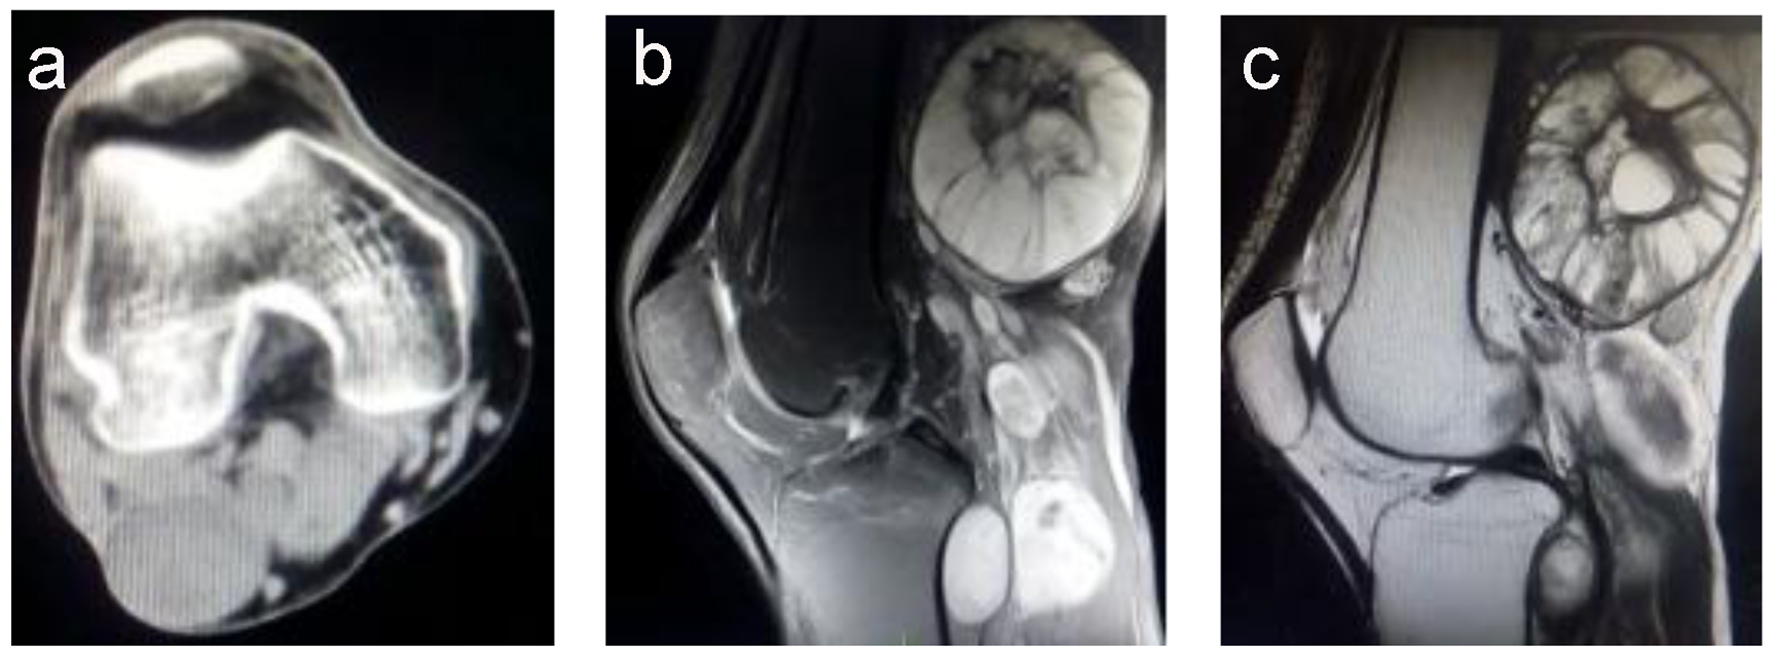

Computed tomography (CT) revealed several unequally sized lobulated and cystic-solid masses below the right popliteal muscle, with the largest mass measuring 3.7 × 4.5 cm; the masses exhibited a homogeneous density and a clear border (Fig. 1a). No bone hyperplasia or destruction or hardening of the right femur and tibia and fibula were detected; however, enhancement was detected at the edge, a part of the calcaneal bone, and formation of depression. Thus, a diagnosis of borderline or poorly differentiated malignant fibromatosis was established by a professional radiologist.

![]() Click for large image | Figure 1. (a) A computed tomography image showing multiple masses with homogeneous density and no bone destruction, with a maximum size of 7.0 × 6.1 cm. (b) A T2-weighted magnetic resonance imaging scan showing a higher signal intensity, with the mass showing an uneven signal and well-defined margins. (c) A T1-weighted magnetic resonance imaging scan showing a slightly higher signal intensity, with the mass showing an uneven signal and liquefaction at the center. |

Magnetic resonance imaging (MRI) showed multiple nodules of varying sizes, mass shadows, and border finishing at the hip, iliac spine, and right tibia and fibula; T2-weighted imaging showed a slightly higher signal intensity (Fig. 1b), and T1-weighted imaging showed a low signal intensity (Fig. 1c). Fat suppression sequence images showed a slightly higher intensity signal; the masses had uneven signals with the largest detected in the right popliteal fossa measuring approximately 7.0 × 6.1 cm2. The tibia and fibula signals were uniform. The tumor borders were well-defined. The soft tissue surrounding the masses demonstrated normal signal intensity. No enlarged lymph nodes or distant metastases were identified. The MRI findings suggested multiple neurofibromas. Therefore, the patient was diagnosed with NF1 and indicated for surgery to resect the tumors.